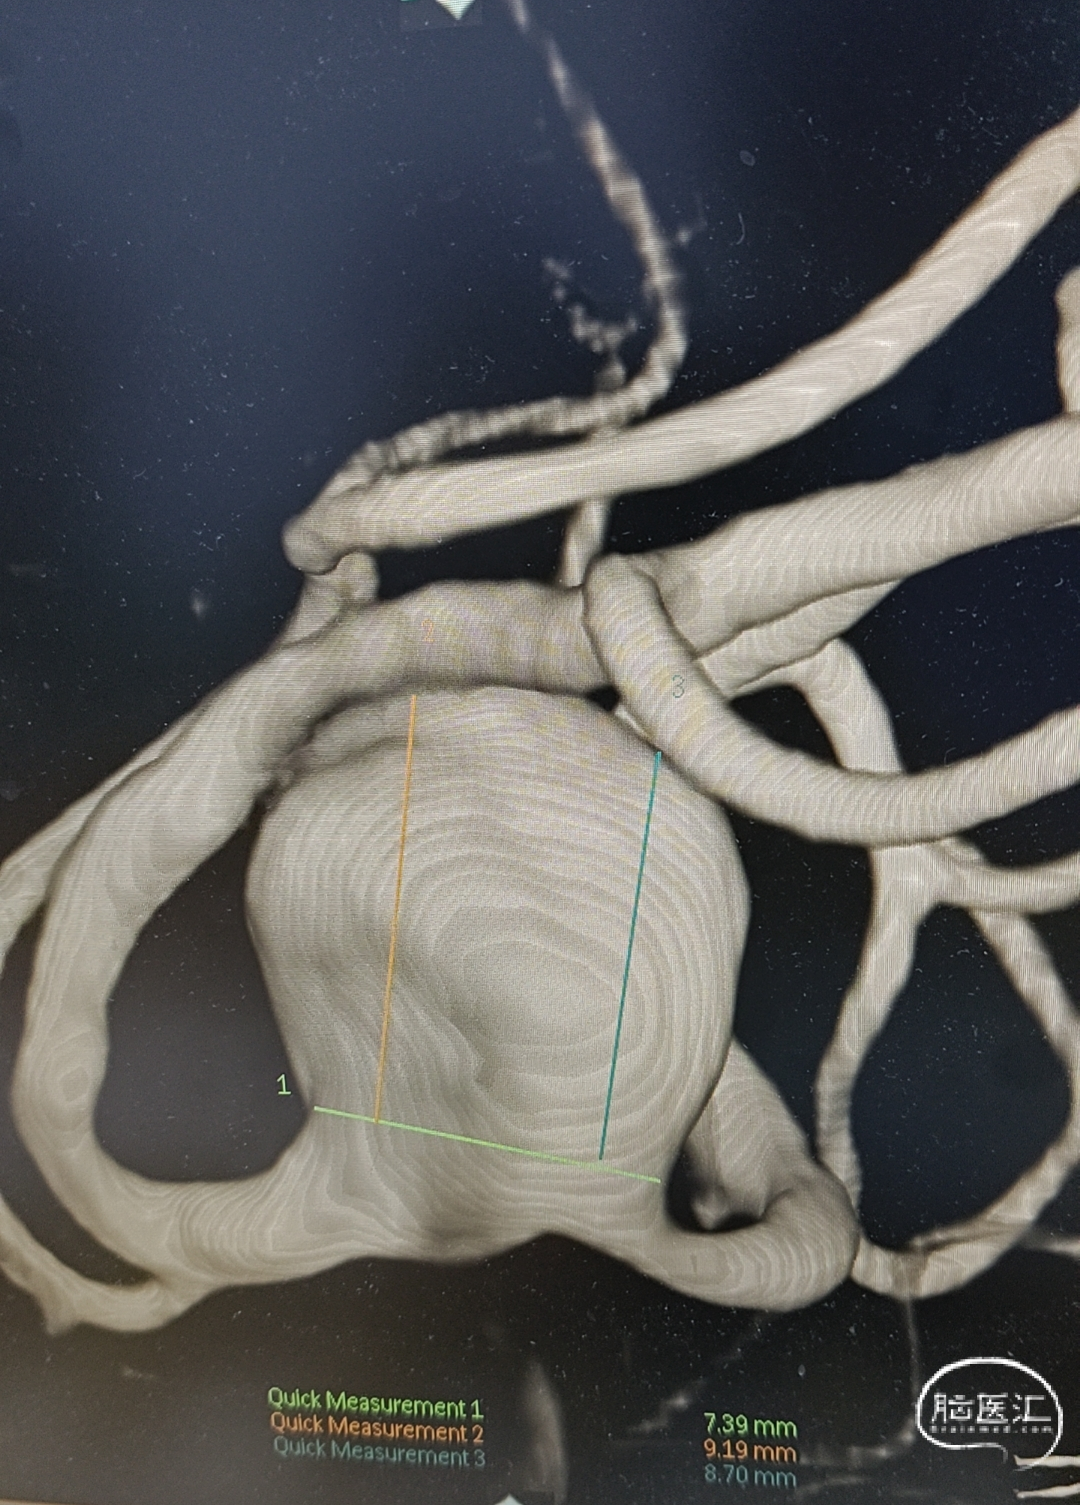

3、辅助检查:头部CTA(外院)提示左侧大脑中动脉M1段分叉处动脉瘤。

术前影像检查

WEB™ SL 11mm*7mm